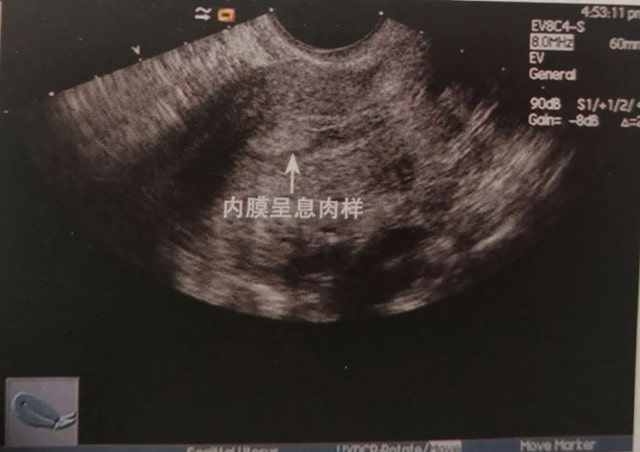

子宫内膜增生症是子宫内膜一种病态的异常的增殖,是妇女的常见病、多发病,通常是由于内分泌失调,导致没有排卵而出现的无排卵型月经的表现,多见于青春期和绝经过渡期。

子宫内膜增生分为单纯型、复杂型与不典型增生:

1、 单纯性增生是子宫内膜对体内的雌激素升高状态生理反应,多因无排卵月经引起,多见于月经初潮或绝经期前的女性。

2、 复杂性增生是由于腺上皮增生引起腺腔内呈乳头状或向间质出芽样生长,约3%可发展为腺癌。

3、 非典型增生是腺上皮细胞层次增多,细胞极其紊乱,三分之一的患者可发展为腺癌。

正常的子宫内膜有增生期、分泌期。而单纯性的内膜增生,说明子宫内膜没有分泌期,没有受到孕激素的影响而转化。容易导致在月经周期规律的基础上出现月经量过多、经期延长或者月经淋漓不尽等临床症状。

单纯性子宫内膜增生是一种比较常见的妇科疾病,是子宫内膜增生中最轻的一种病理类型。主要指子宫内膜在雌激素的持续刺激下,内膜增厚了不脱落,导致增生的一种疾病。但子宫内膜单纯性增生的女性除了不规则的阴道出血外,其他症状很少见。